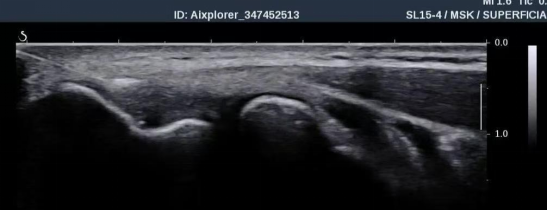

超声引导下PRP注射治疗